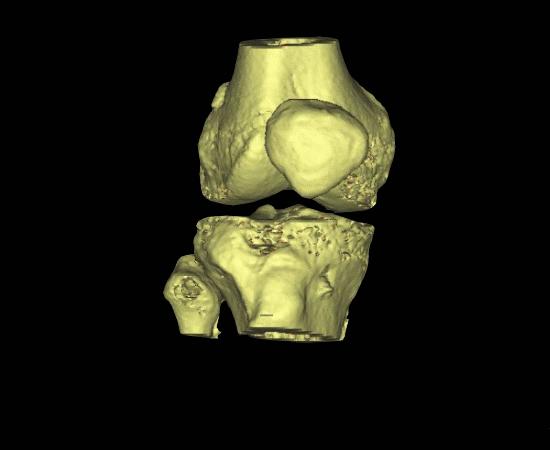

髌骨的活动是有轨迹的,正常情况下,它都待在一个类似于轨道的凹槽里,叫做股骨滑车。同时,依靠髌骨上下左右相连肌腱及韧带组织,将髌骨平衡在居中的位置上。

这种先天性的发育不良根据严重程度,有不同的表现。

有一部分人从出生起髌骨就脱在外面,长大后无法正常行走,这种是先天性的髌骨脱位,在婴幼儿时期就能发现。

有一部分人会表现为习惯性髌骨脱位,每次屈膝时髌骨会脱出来,再伸膝又会归位。

这两类髌骨脱位畸形较为严重,症状明显,一般都能及时被发现并就诊。容易误诊和漏诊的同时也更多人患病的是复发性髌骨脱位。